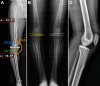

Background: In bifocal varus deformity, double-level osteotomy (DLO) is advocated to treat lower limb alignment to prevent an adverse increase in joint line obliquity.

Methods: Inclusion criteria were medial tibiofemoral compartment pain, varus knee deformity with an abnormal medial proximal tibial angle <84° and a lateral distal femoral angle >90°, a functional anterior cruciate ligament, failure of nonoperative treatment, and a minimum 2-year follow-up with all clinical and radiological data. The rate of return to work or sports; the Knee injury and Osteoarthritis Outcome Score (KOOS); the University of California, Los Angeles (UCLA) activity score; and patient satisfaction were assessed at a minimum of 2 years of follow-up. Statistical comparison of the 2 groups was made using the chi-square or Student t test.

Results: A total of 69 consecutive patients were analyzed, of whom 38 underwent OWHTO and 31 underwent DLO surgery. A significant between-group difference was found for all radiological parameters; in particular, there was less joint line obliquity after DLO compared with OWHTO (1.7° vs 5.6°; P < .001). DLO provided better outcomes compared with OWHTO regarding the UCLA score (4.3 vs 6.7; P < .001) and patient satisfaction (2.6 vs 3.9; P < .001), but no significant difference in KOOS or return to work or sports was observed. The OWHTO group had more hinge fractures than the DLO group (34.2% vs 12.9%; P < .001).

Conclusion: For combined tibial and femoral varus deformity, DLO produced more physiologic joint line obliquity with slightly improved UCLA and patient satisfaction scores. A greater incidence of hinge fracture was observed after isolated OWHTO compared with DLO due to a larger tibial correction; however, this had little effect on clinical results at the 2-year follow-up.